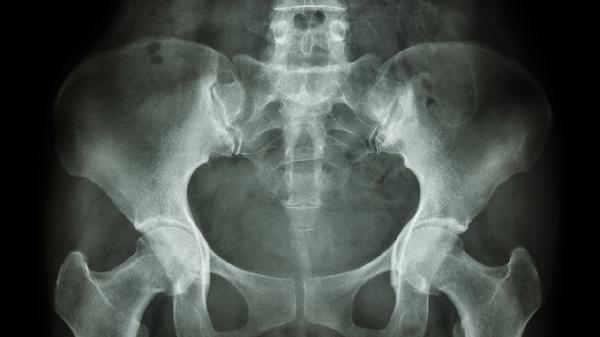

骨盆上方边缘疼痛的原因是什么

骨盆上方边缘疼痛可能与肌肉劳损、韧带拉伤、盆腔炎、腰椎间盘突出、泌尿系统结石等因素有关。疼痛通常表现为局部钝痛、活动受限或放射性疼痛,建议及时就医明确诊断。